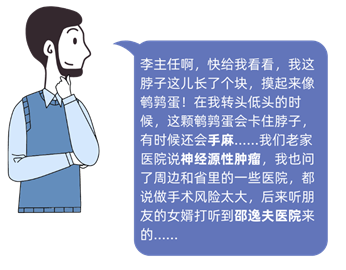

患者张先生一进到神经外科李新伟主任医师的诊室,就指着脖子开始倾诉。

李新伟主任医师摸了摸张先生脖子上的肿块,圆滚滚的,还有一定的活动度,李医师建议张先生住院治疗。